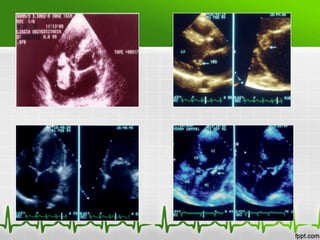

Endocarditis infecciosa

Ecocardiograma

•   Sensibilidad (60-70%) para vegetaciones

•   Aumenta con ETE

•   No detecta vegetaciones <2mm

•   Un estudio negativo no excluye

•   Util para indicar Tto. Quirurgico

•   Diagnóstico de complicaciones

Ecocardiografía

 Ecocardiograma Transtoracico (ETT)

-Sensibilidad 46% y especificidad de 95%

– Primera linea en sospecha de EI.

– Mayor rendimiento en valvulas nativas

– ETT no descarta EI.

• Ecocardiograma Transesofágico (ETE)

-Sensibilidad del 93% y especificidad del 96%

– Mayor sensibilidad

– Indicado v. protesicas

– Complicaciones cardiacas

– Dudoso ETT

– Bacteremias por Hongos o S. aureus

• Existen 3 hallazgos ecocardiográficos que constituyen criterios

mayores para el diagnóstico de la EI:

a) una masa móvil y ecodensa unida al endocardio valvular o mural

o a material protésico implantado.

b) evidencia de abscesos o fístulas.

c) la dehiscencia de una prótesis valvular de nueva aparición,

especialmente si ocurre a largo plazo tras la implantación.